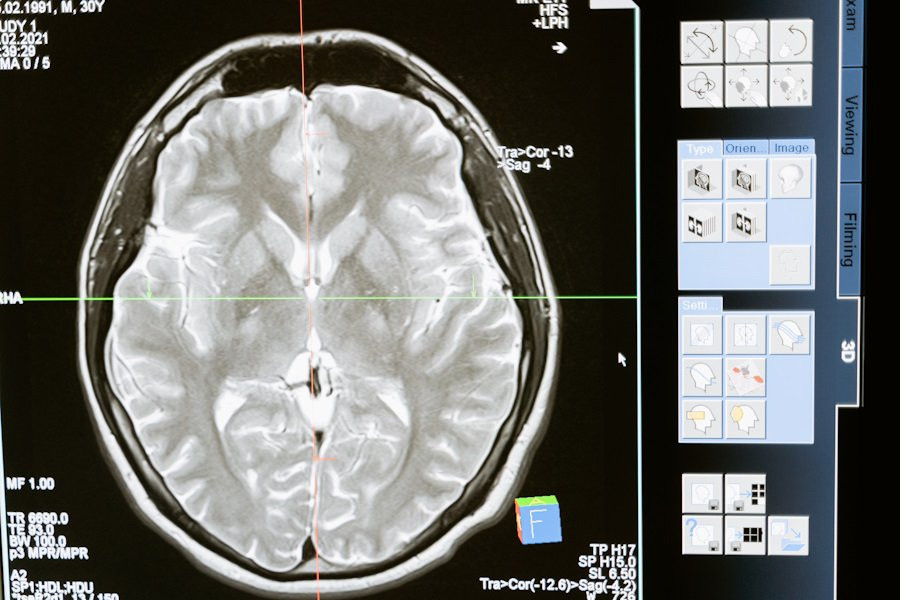

Исследователи из Mount Sinai School of Medicine и The Rockefeller University обнаружили в мозге механизм, который позволяет кокаину и морфию захватывать системы обработки вознаграждения, вытесняя естественные формы удовольствия. Открытие опубликовано на портале Science.

"Мы обнаружили, что кокаин и морфий нацеливаются на те же клетки мозга, что и еда или вода, вызывая изменения в их работе", — объясняет исследователь Эрик Дж. Нестлер. Они выяснили, что наркотики вызывают более сильные реакции в этих клетках, чем естественные стимулы, такие как еда или питье.

Это исследование проводилось на мышах, которые были наркозависимыми как от кокаина, так и от морфия. Они обнаружили, что даже после прекращения приема наркотиков, клетки мозга сохраняли нарушенную реакцию на естественные вознаграждения.

Исследователи также выявили ген, который играет ключевую роль в этом процессе, предоставляя новую надежду на разработку лечения для наркозависимости.